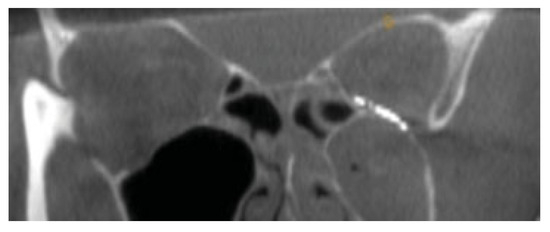

Figure 2.

Coronal section of orbital floor fracture in Case 1.